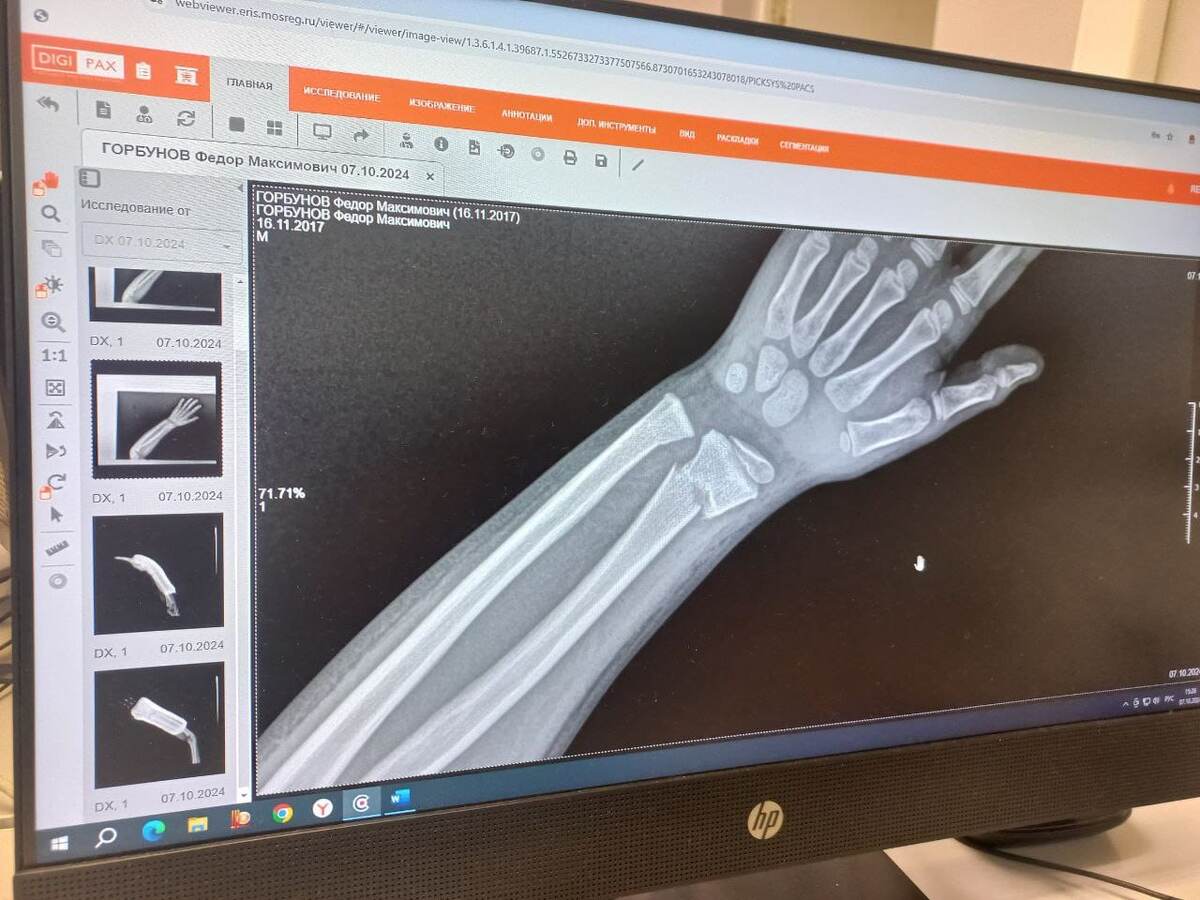

Снимок до лечения